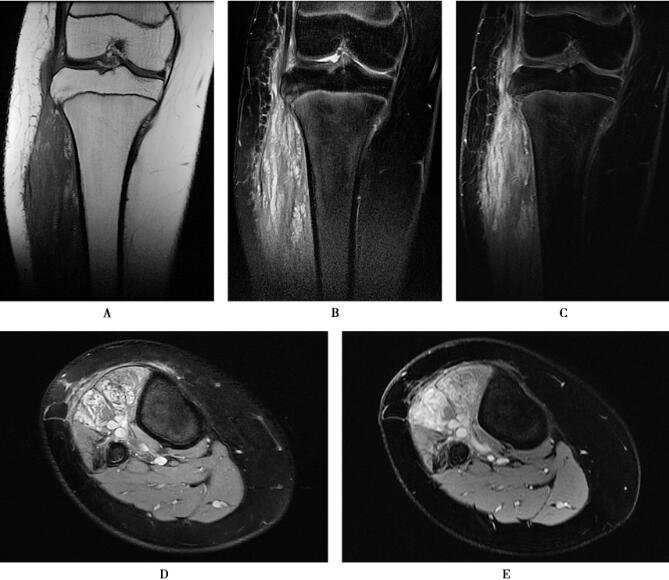

图1 下肢软组织内血管瘤

MRI显示右侧膝关节及胫骨外侧可见以团片状等T1WI稍高、等信号,T2WI高、等混杂信号,边缘与周围软组织分界欠清,大小约为2.8cm×3.4cm×11.5cm,增强扫描病灶显著不均匀强化。

CE-MRA显示粗大的供血动脉、畸形血管团和迂曲扩张的引流静脉,皮下脂肪内可见曲张静脉。